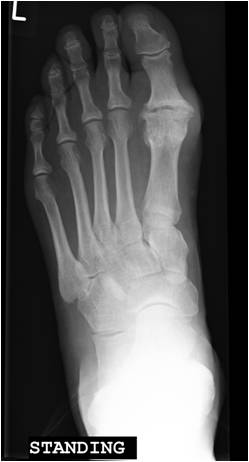

If the disease is more advanced either a joint fusion (arthrodesis)(Fig 3) or a joint replacement (Fig 4) can be considered. The former leaves the joint stiff but pain free, whereas the latter involves implanting an artificial joint which allows some joint movements whilst reducing or eliminating pain.

Big toe joint replacement surgery takes a similar amount of time to recover from, weight-bearing in a protective shoe is required for 4-6 weeks and toe exercises are started early.